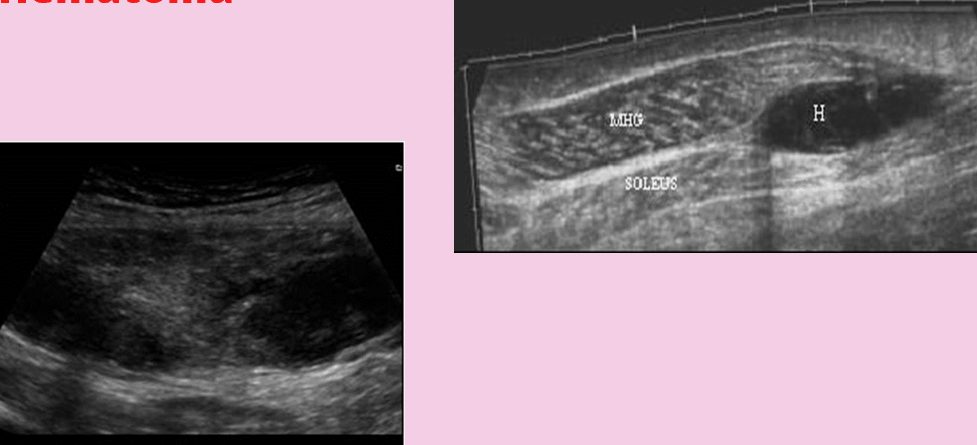

this shows

soft tissue edema

leg swelling

associated with CHF

what is this?

hematoma

can be cystic, solid or complex